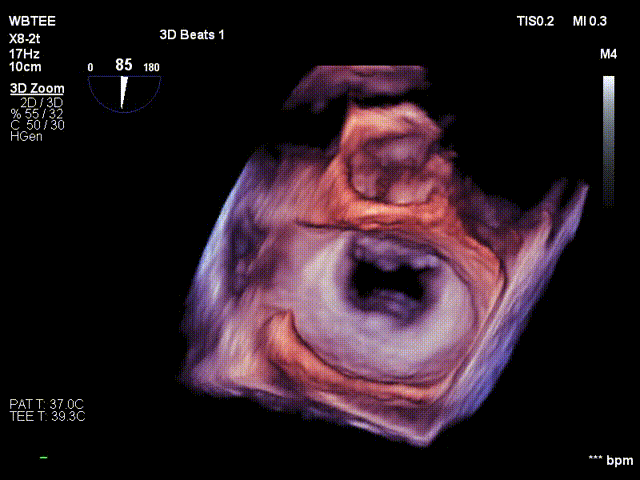

患者全身麻醉消毒铺巾后,建立右侧股静脉入路,在经食道超声指导下精准穿刺房间隔。将可操控导引导管和二尖瓣夹XTR输送系统送入左心房

调整二尖瓣夹轨迹和方向,使其轨迹垂直于二尖瓣环平面且指向心尖,定位于二尖瓣2区且6-12点钟方位

在食道超声王蓓主任的紧密配合下,经食道超声引导后傅国胜教授使用二尖瓣夹准确成功捕获前叶A2和后叶P2反流最严重区域,并予夹合,使二尖瓣在收缩期由大的单孔变成小的双孔,显著减少了二尖瓣反流。